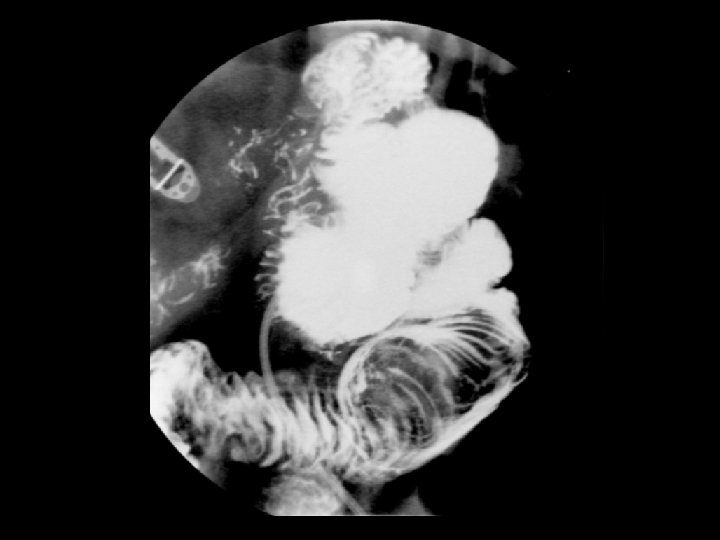

Intussusception • Findings: – Low density intraluminal mass within a small bowel loop – Contrast surrounding this mass produced the “coil spring” appearance – Associated with a lead point in adults: • Lipoma • Carcinoma • lymphoma • Meckel’s diverticulum